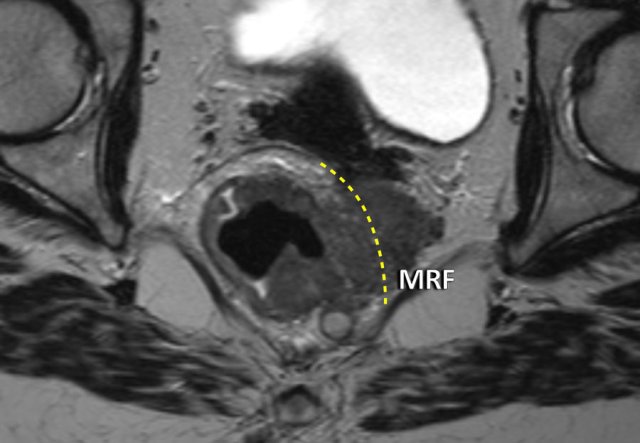

Example of a pathologic lymph node measuring 9 mm in the left obturator space (arrow).

This node needs to be irradiated or resected separately to avoid recurrence.

This axial T2W-image is of a patient who was treated with a TME.

There is a local recurrence of rectal cancer due to an untreated positive lateral lymph node